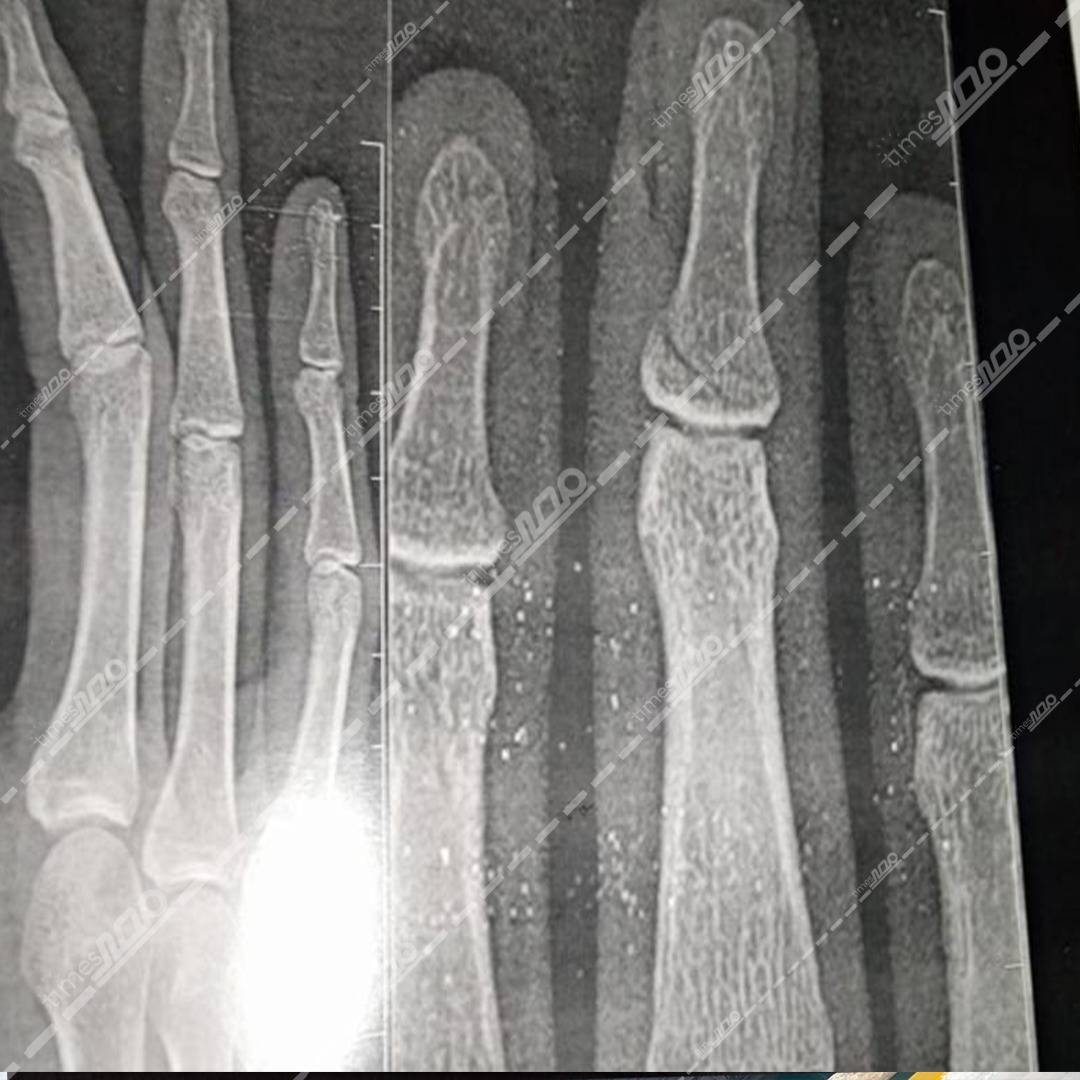

حصل "مصر تايمز" على صور الأشعة التي أجراها طبيب جراحة على يديه، بعد التعدي عليه من قبل أسرة مريض أثناء عمله داخل مستشفى قنا العام، والتي وضحت كسر في أحد صوابعه.

وعلى الفور انتقلت قوة أمنية برئاسة المقدم محمود حمد الله، رئيس مباحث قسم قنا، إلى المستشفى وتبين إصابة طبيب جراحة، بكسر في أحد صوابعه وكدمات بالوجه إثر التعدي عليه من أسرة مريض.